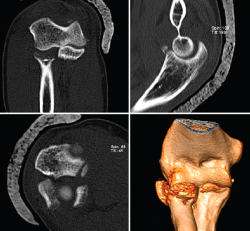

Figura 14. Tríada terrible de codo derecho donde puede apreciarse en las imágenes de tomografía computarizada la fractura de la cabeza del radio, la fractura de la coronoides y la subluxación posterolateral de la ulnohumeral.